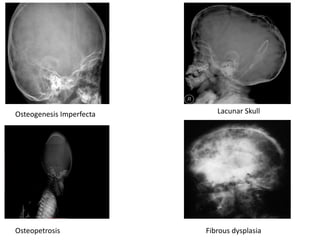

ABNORMAL DENSITY

Generalized reduced density

• Osteogenesis Imperfecta

• Lacunar skull – focal areas of nonossified bone bound by normally

ossified bone

Generalized Increased density

• Osteopetrosis – basal bone initially, followed by calvaria

Localized increased density

• Fibrous dysplasia

Osteogenesis Imperfecta Lacunar Skull

Osteopetrosis Fibrous dysplasia